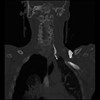

23 ANGIO,CE,Cor-MIP,5.000,ANGIO,Cor-MIP,